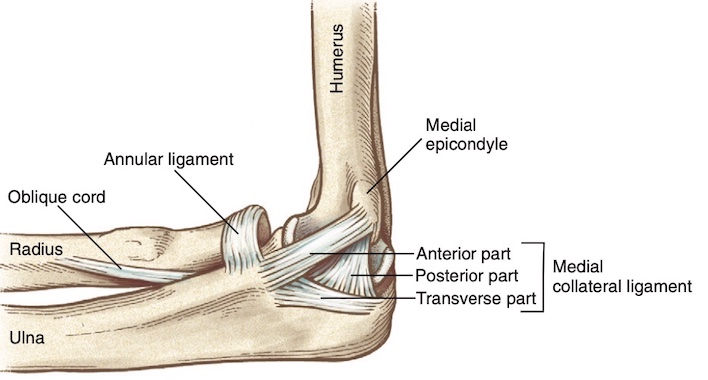

- Dây chằng bên trong , hay dây chằng bên trụ, bao gồm ba phần: đoạn trước, sau và ngang. Bó trước là thành phần mạnh nhất và nổi rõ nhất, trong khi bó sau là sự dày lên của phần sau của bao khớp và cung cấp sự ổn định ở góc gập 90 độ.

- Phức hợp dây chằng bên ngoài bao gồm dây chằng bên quay, dây chằng vòng quay (annular ligament), và dây chằng bên trụ ngoài (lateral ulnar collateral ligament). Dây chằng bên trụ ngoài đóng góp nhiều nhất vào sự ổn định ở mặt ngoài của khớp khuỷu. Tổn thương cấu trúc này có thể dẫn đến mất vững xoay sau ngoài.

- Các thành phần làm vững chính của khớp khuỷu bao gồm khớp cánh tay trụ, dải trước của dây chằng bên trong, và dây chằng bên trụ ngoài.

- Dây chằng bên trụ rất quan trọng bảo vệ bên trong, phòng ngừa dạng khuỷu khi bị lực tác động trong các hoạt động. Nhiều môn thể thao tiếp xúc và hoạt động gây sức ép lên mặt trong khớp, gây chấn thương.

- Dây chằng bên quay làm vững bên ngoài và ít khi bị chấn thương.

- Dây chằng vòng quay ôm quanh chỏm xương quay để giữ vững.